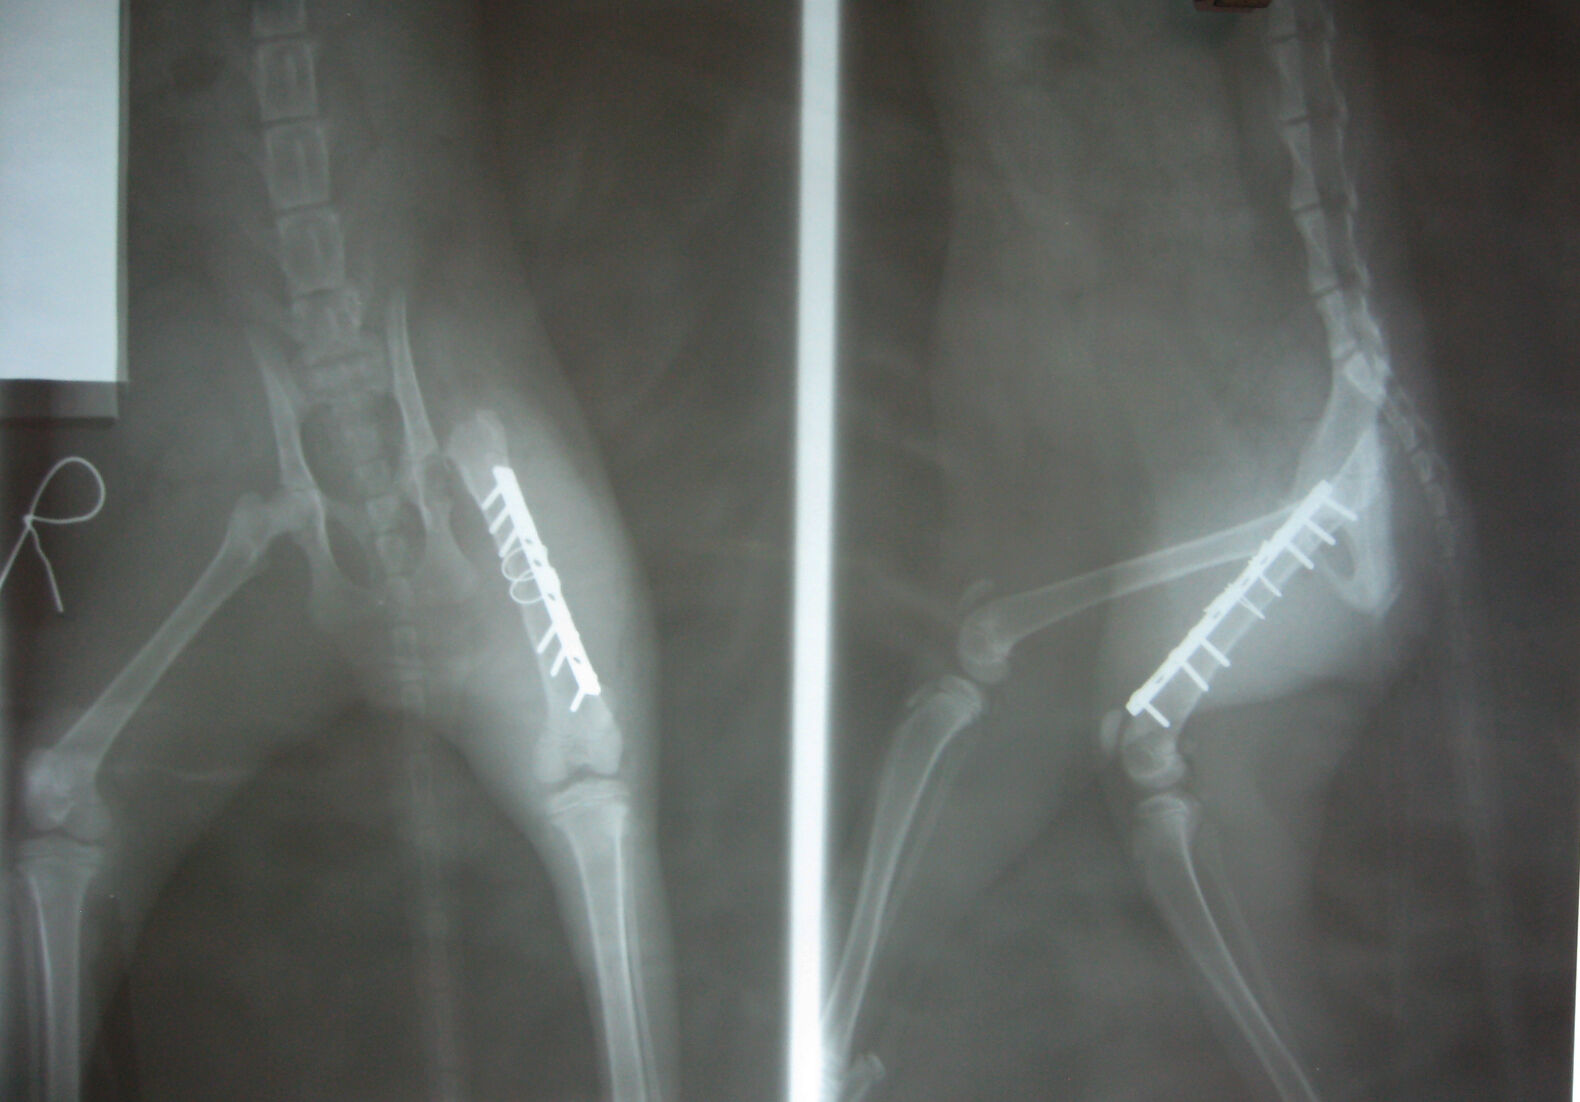

我用外套包起連忙送去醫院,醫生也緊急拍了X光檢查,發現小貓腿骨斷裂,股骨向上穿刺,膀胱也擠到腹腔造成赫尼亞。

手術分了2次進行。第一次動了腿骨骨折修復及股骨切除的部份,第2次修補腹腔赫尼亞。我問醫師為何不一次完成,醫生說,腿骨修復手術就花了好久的時間才完成,再加上貓咪年繼很小,太久的手術對貓咪來說是種風險,所以才分2次進行。